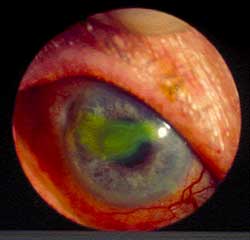

Rycina 3. Wygląd rogówki:

przed leczeniem

w 7. dobie

w 14. dobie

Klinika Chorób Oczu AM w Warszawie jako jedyna w Polsce wykorzystuje metodę fotodynamiczną do leczenia niektórych schorzeń przedniego odcinka. Metodę fotodynamiczną z fotouczulaczem ALA stosujemy jako terapię uzupełniającą między innymi u pacjentów z przewlekłym wirusowym zapaleniem rogówki i owrzodzeniami troficznymi rogówki.

Mały wałeczek maści umieszczany jest w worku spojówkowym chorego oka, które następnie zasłaniane jest opatrunkiem na 2 godziny. Po tym czasie barwnik zostaje aktywowany światłem lasera He-Ne. Seanse lecznicze powtarzane są po 7-14 dniach w zależności od stopnia gojenia się ubytków.

Klinicznie bezpośrednio po leczeniu w większości przypadków występuje znaczne zadrażnienie spojówek i brzegów powiek oraz delikatny obrzęk rogówki w miejscu zmian. Objawy te ustepują po około 24 godzinach. Stopniowy proces gojenia obserwowany jest po 2-3 sesjach leczniczych w przypadku drobnych ubytków i 5-6 w przypadku rozległych owrzodzeń.